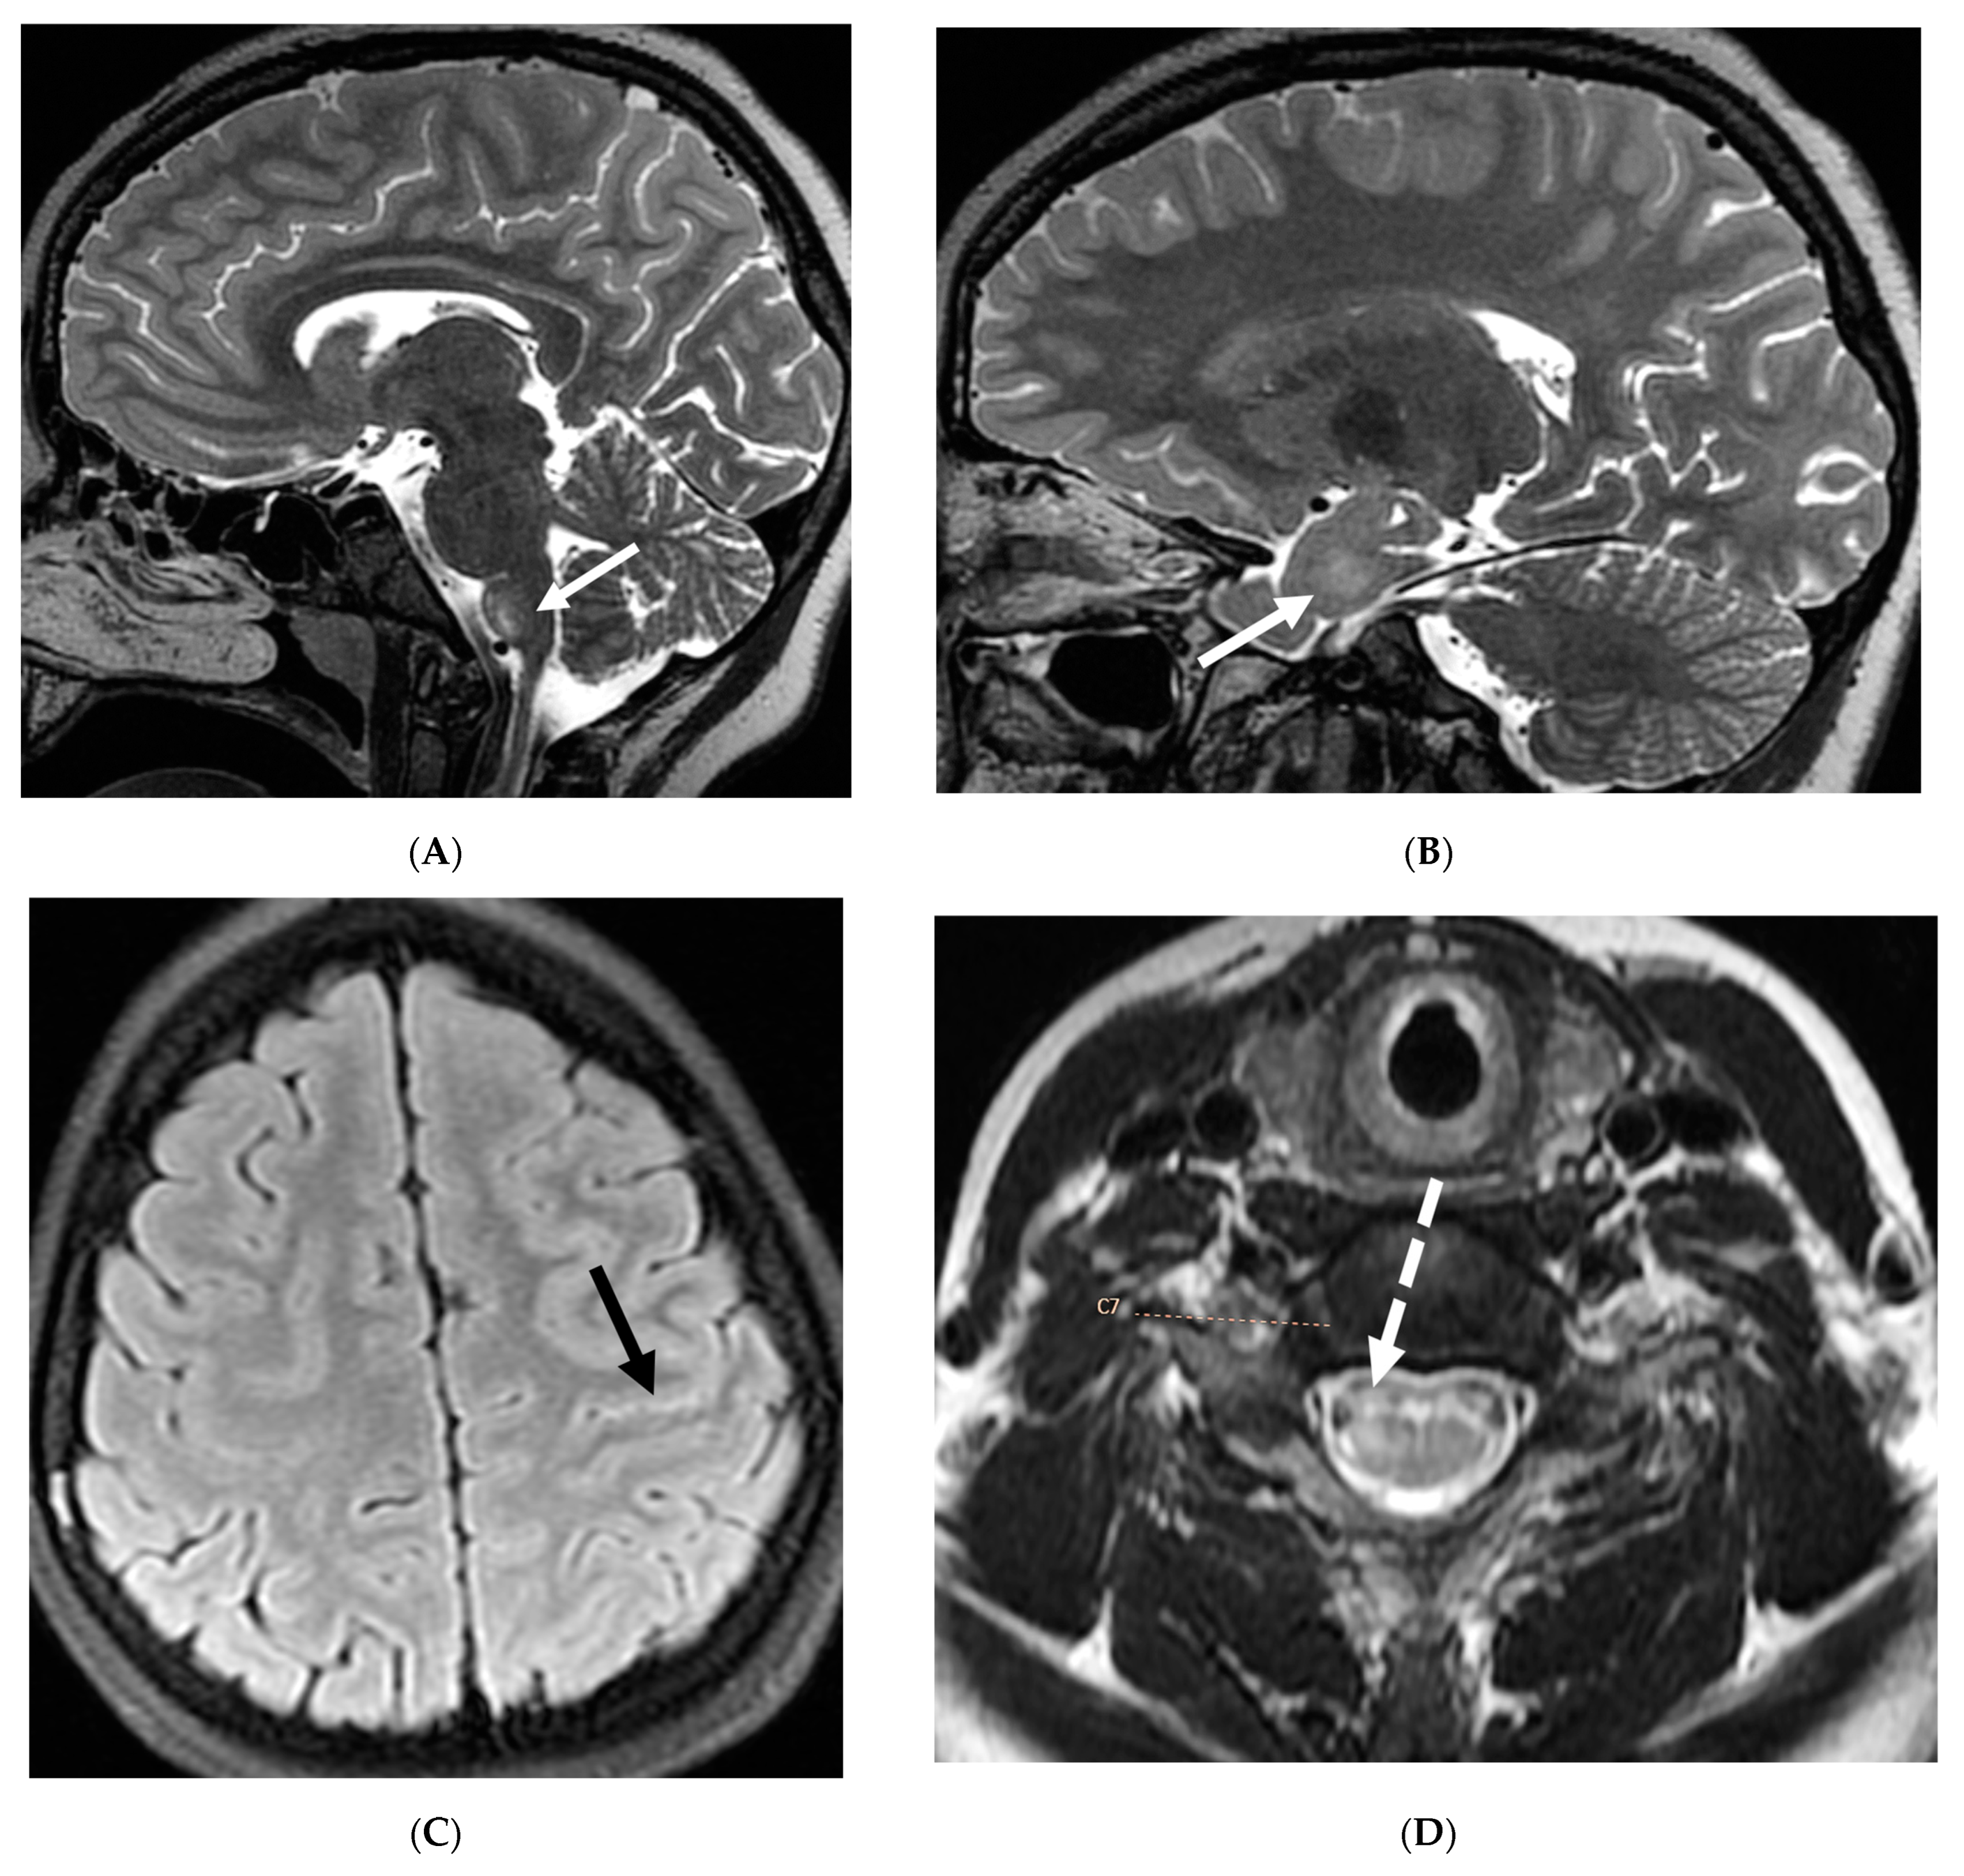

Anti-MOG antibody associated demyelination (MOGAD) frequently presents as Acute Disseminated Encephalomyelitis (ADEM) in children and opticospinal involvement in young adults [105]. Bilateral but asymmetric T2 hyperintense lesions occur in thalamus, pons and cerebellar peduncles are common in children [106]. Optic nerve involvement typically presents as a long segment with anterior predominance, in contrast to the posterior predominance seen in Neuromyelitis Optica Spectrum Disorders (NMOSD) and the short segment involvement characteristic of Multiple Sclerosis (MS) [106].

LME has been shown to present early in the disease course and is much more common in children (33%) compared to adults (8%) [107]. Gadde et al. found that 8% of pediatric MOG antibody-associated demyelination cases had only LME without any other central nervous system manifestation. LME when present can be particularly helpful in differentiating from NMOSD [106]. Furthermore, Valencia-Sanchez et al. reported a significant association between LME and cerebral cortical encephalitis in MOG antibody-associated disease. This finding suggests that LME may be an important marker for cortical involvement and potentially more severe disease (Figure 21) [108].

Figure 21.

Sagittal T2 (A,B), axial FLAIR (C), axial T2 cervical spine (D) at the level of C7 vertebral body and Axial T2 orbits (E): 12-year-old girl presented with right focal motor seizure and left temporal lobe slowing on electroencephalogram (EEG). Right eye vision loss and irritability. Ill-defined areas of signal abnormalities are identified within the RIGHT mesial temporal lobe and bilateral medulla (white arrows). FLAIR hyperintensity is identified on the left central sulcus (black arrow). Small focus of signal abnormality is seen on the right side of the cord at the 7th cervical vertebra (C7) (dashed arrow). There is also bilateral papilledema (arrowheads). Post contrast axial T1 (F,G), axial T1 orbits (H) and axial T1 cervical spine at C7 (I): Asymmetric LME (black arrows) predominantly involving the left cerebral hemisphere, with minimal right parietal involvement is seen. Ill-defined enhancement in the right mesial temporal lobe, and right greater than left medulla (white arrows) corresponds to the signal abnormality. There is right greater than left, optic nerve enhancement (curved arrow). Single small enhancing lesion in the spinal cord on the right at the level of C7 corresponds to the signal abnormality (dashed arrow). Features favor a demyelinating process. MOG antibodies were positive at 1:20 in keeping with Myelin oligodendrocyte glycoprotein (MOG) antibody disease (MOGAD).